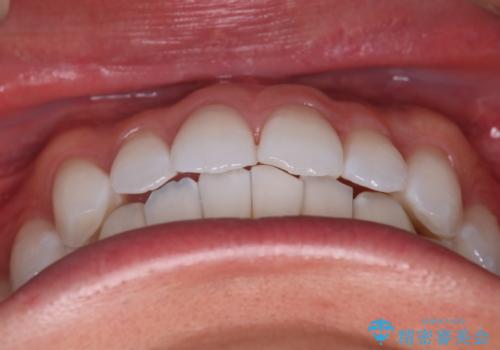

- がたつきが気になるとの事で来院されました。

目立たない装置で費用も抑えたいとの希望があったため、インビザラインにて治療をすることとなりました。

上下顎ともにIPR(歯と歯の間を削る処置)を行い歯並びを整える治療計画を立てました。

治療当初は、計画通りに治療が進むか心配でしたが、しっかりマウスピースを使用していただいたことで

治療期間も長引くことなく歯並びを綺麗に改善することが出来ました。

患者様の希望もあり、前歯の微調整で1回リファイメント(マウスピースの再発注)を行いました。